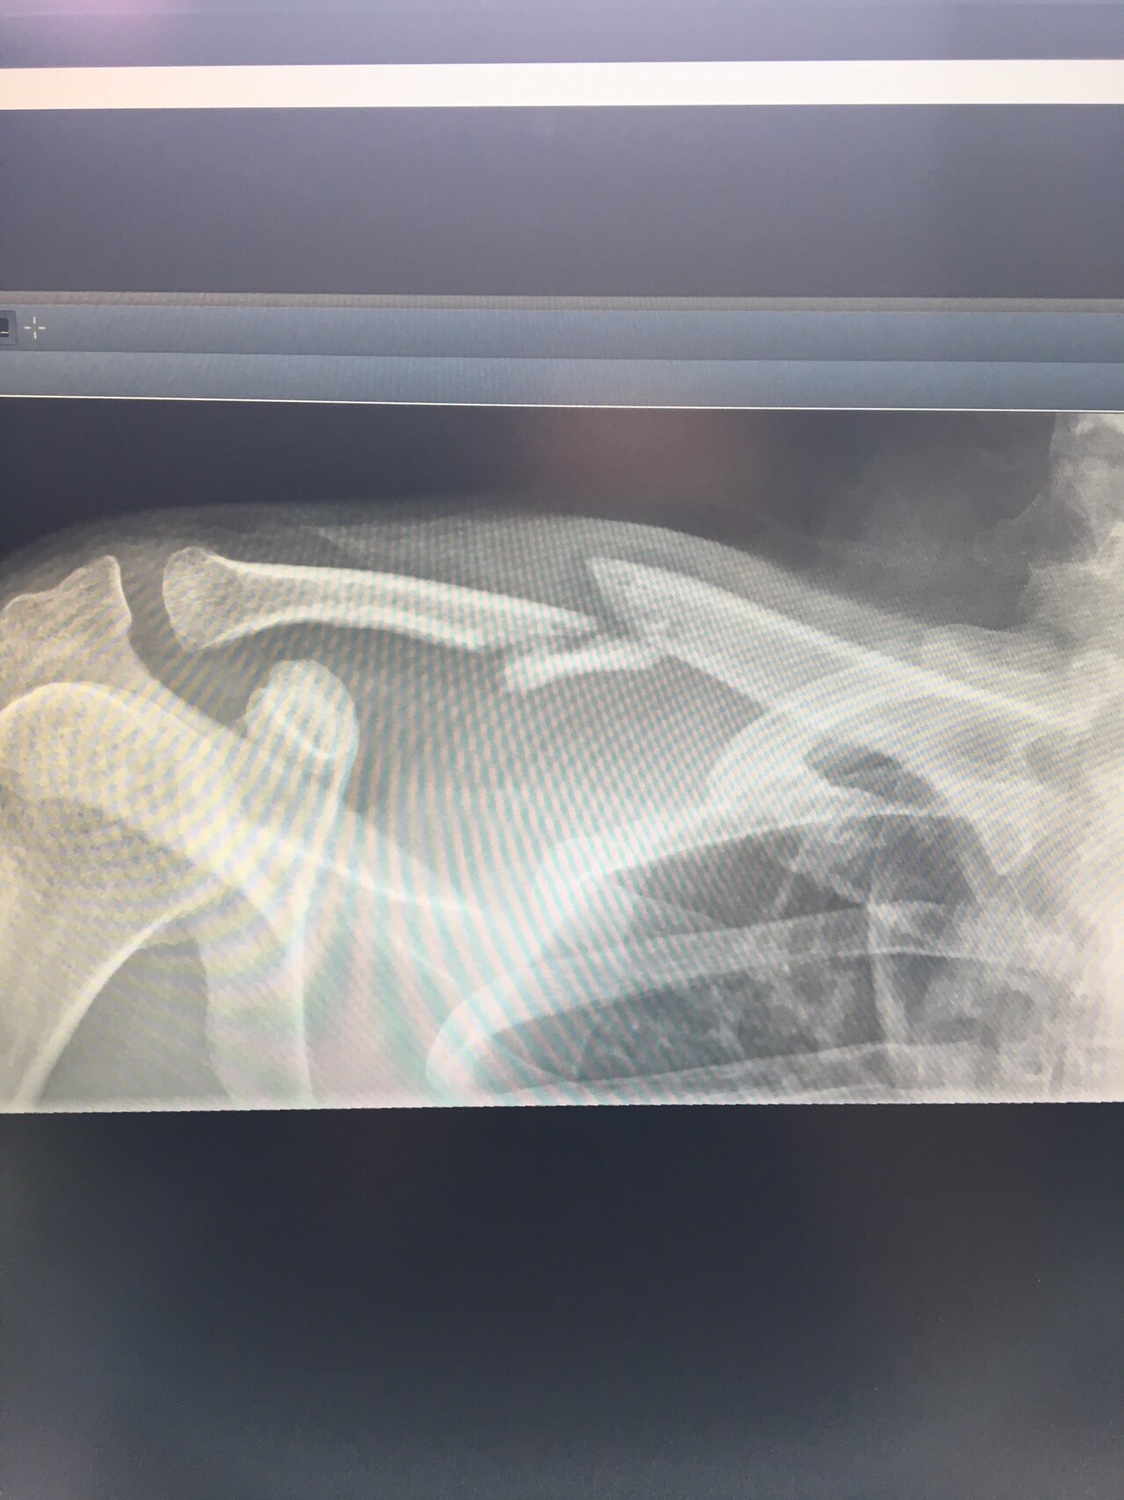

Udo-MH hat geschrieben:Also ich kann ja mal meine 2 cent beisteuern. Auch wenn es nicht das gleiche ist. Ich hatte einen Clavicula RE Trümmerbruch. Die Erste OP war gelaufen und mir wurde eine viel zu dünne Titanplatte eingeschraubt. Die Trümmer von der Assiärztin mit Nähfaden umwickelt. Wenn gewünscht hau ich auch Röntgenfotos rein, was aber für mich zweitrangig ist.